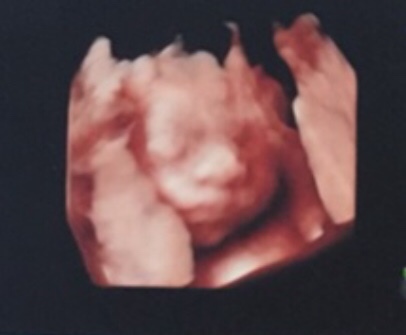

孕34周+5天

孕35周+1天